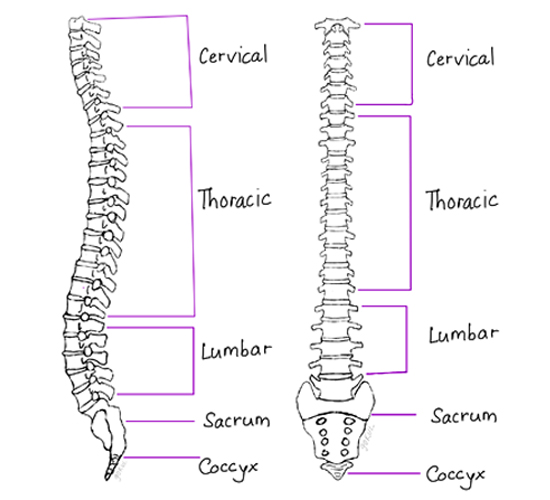

The spine (vertebral column) is made up of several bones called vertebrae which are stacked one upon another. Each vertebra is joined to the vertebrae above and below by two pairs of joints called the facet joints situated on the two sides. The typical vertebra has a solid body in front and two plate-like structures on two sides at the back called laminae. The laminae meet in the midline to form a protrusion, the spinous process, which can be felt through the skin of the back. On the two sides each lamina is joined to the body of the vertebra by a short bony stud called the pedicle, thus completing a bony ring. These rings inside each vertebra join together to form a tube called the spinal canal through which passes the spinal cord and the nerve roots.

A small gap, the intervertebral foramen, is present in between the adjacent pedicles for the passage of the nerve roots. These nerve roots are the connections that carry all sensations from the body to the brain and also bring commands from the brain to muscles resulting in movement. In between two adjacent vertebral bodies there is a strong rubber like tissue (Cartilage), resembling a washer, called the intervertebral disc. The nerve root in the intervertebral foramen lies just behind the disc. A disc has a stronger outer part called the annulus fibrosus and a softer jelly-like central part called the nucleus pulposus. When a patient has a prolapsed disc, the central soft part of the disc bulges out and can press on the nerve root/s.